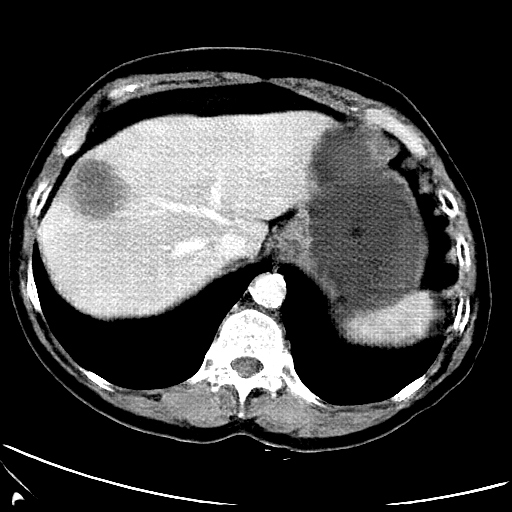

Refer to caption

CT

MRI

Figure 7: Lossy image reconstructions on CT (row 1, 2) and MRI (row 3, 4) images, where the row 2, 4 provide a zoomed-in view of the bounding box region of the row 1, 3. The leftmost column represents the target images, while the subsequent four columns show the stolen images reconstructed by the decoder D or D1 in two scenarios.

A visual comparison between target and stolen images is available in Fig. 7. We observe that the stolen images from IT Scenario closely resemble the input ones, particularly in the tumor regions, whereas stolen images from EP Scenario exhibit blurring artifacts in finer details. In both cases, the stolen images reconstructed by D1D1 demonstrate a comparable quality to those reconstructed by DD, thus further confirming the effectiveness of the reduced decoder D1D1.